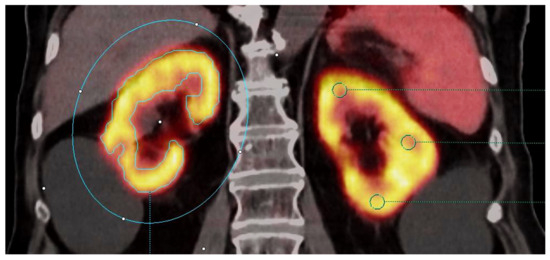

2.4. Molecular Imaging Parameters Collected

2.5. Morphologic Parameters Collected